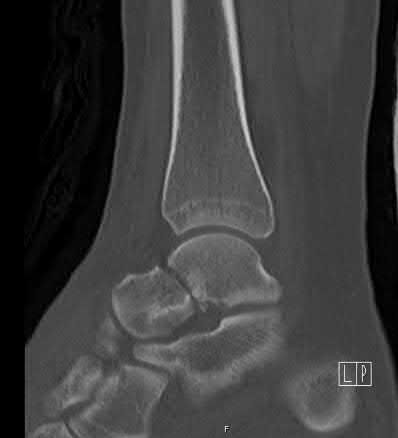

A 28-year-old male sustains a severe hyper-dorsiflexion injury to his ankle in a motor vehicle accident, resulting in a Hawkins Type III talar neck fracture. Which of the following arteries provides the predominant blood supply to the body of the talus, placing it at significant risk for avascular necrosis in this injury?

Correct Answer: Artery of the tarsal canal

Explanation:

The artery of the tarsal canal, which is a branch of the posterior tibial artery, provides the dominant blood supply to the talar body. In a Hawkins Type III fracture (talar neck fracture with subtalar and tibiotalar dislocation), the blood supply from the artery of the tarsal canal, the artery of the sinus tarsi, and capsular vessels are disrupted, leading to an avascular necrosis (AVN) rate approaching 100%.